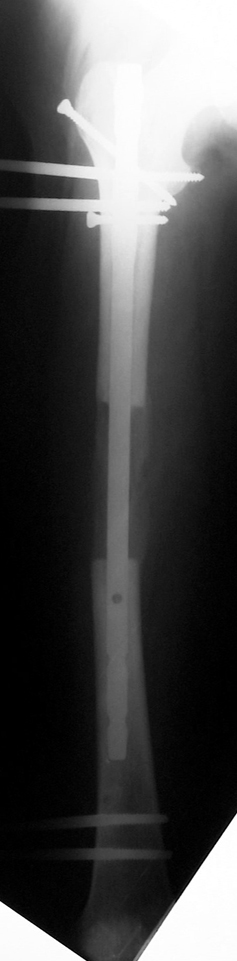

Installment of the intramedullary nail and osteotomy:

The patient lies is supine position at a traction table and legs are crossed with the uninvolved leg at the bottom. The medullary cavity is penetrated through piriform fossa using the standard method, and medulla is reamed 1.5 mm thicker than the nail to be used, over a guidewire. Proximal femur is reamed more, because the intramedullary nail is thicker proximally. The osteotomy site is planned at the X-Rays. It is important that at least 8 cm. of nail remains distal to the osteotomy site after the completion of the lengthening procedure. Percutaneous corticotomy is performed. The guide wire is advanced distally in order to measure the length of the nail. An intramedullary nail of apropriate length is placed. In the end, the nail is interlocked proximally, a suction drain is placed and the fist step of the operation is completed.

The application of the external fixator: Three Schanz screws are placed distally and three screws are placed proximally. At least 1 mm of distance shall remain between the screws and the nail.

In selected cases, we prefer to use a combination of a unilateral dynamic axial fixator and an interlocked intramedullary nail, in order to protect the length and alignment after the completion of the lengthening procedure. As a prerequisite for this technique, the narowest diameter of the medullary cavity shall be wider than 7 mm and the length of the nail segment distal to the osteotomy site shall be at least 8 cm. after the completion of the lengthening procedure.The intramedullary nail neutralizes shear and bending forces on femur during lengthening, shortens external fixation time, and protects newly formed bone against fractures. In our series, subtrochanteric osteotomy was performed in one case. No varus angulation occured despite the intramedullary nail.